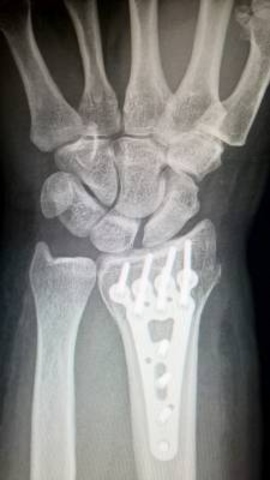

Investigadores del departamento de Ingeniería Minera, Mecánica y Energética de la Universidad de Huelva y del grupo de investigación Ingeniería Mecánica de la Universidad de Sevilla (España) han desarrollado un método que analiza la recuperación en fracturas y otras dolencias óseas con un método que observa el proceso en el nivel de nanoescala. Con los resultados obtenidos se podrá generar un sistema informático que permitirá a los médicos valorar nuevos tratamientos personalizados.